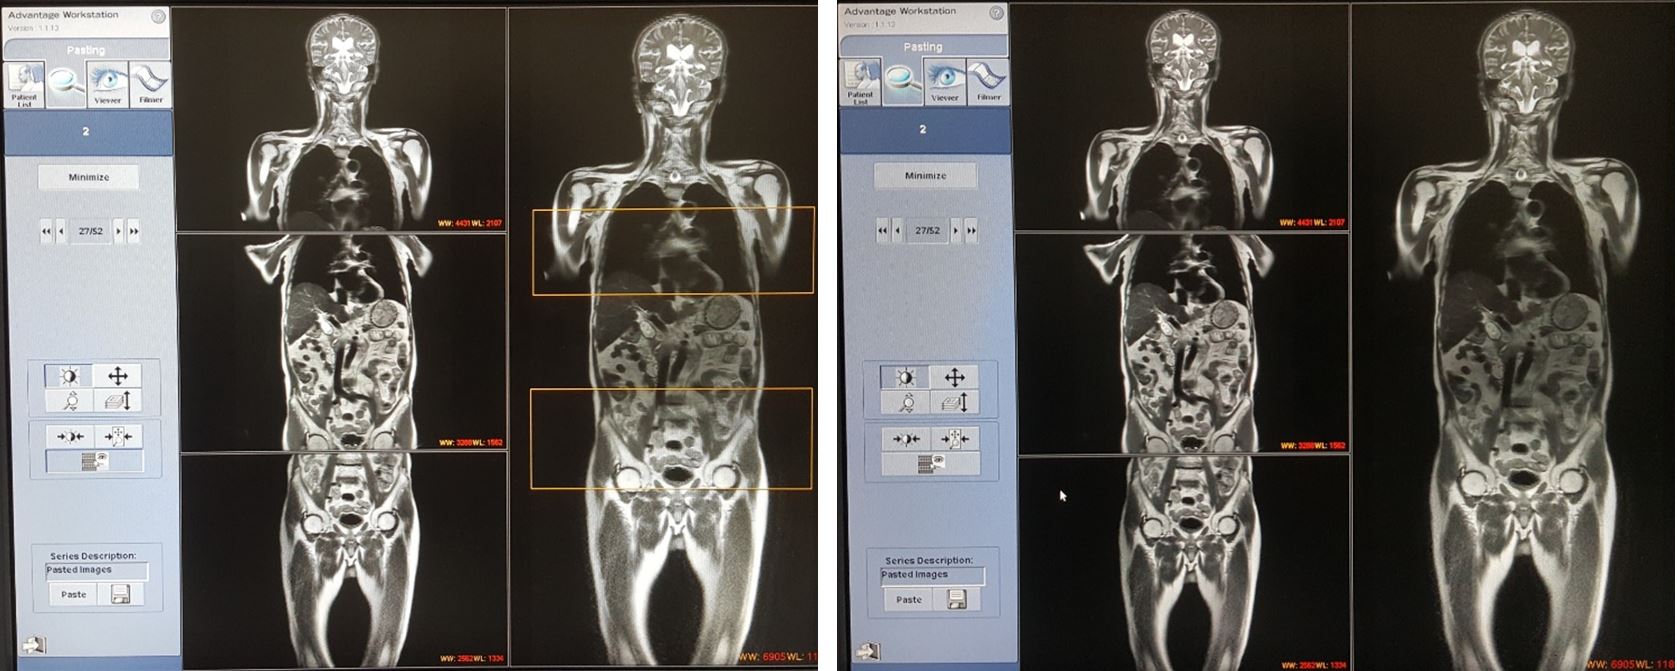

Một số hình ảnh thực tế:

Hình ảnh chụp cộng hưởng từ toàn thân trên bệnh nhân ở Nhà cái cá cược cá độ uy tín, game bài, casino, thể thao, nổ hũ, bắn cá

Chụp và xử lý hình ảnh trên máy cộng hưởng từ tại Hubet com cá cược thể thao 108